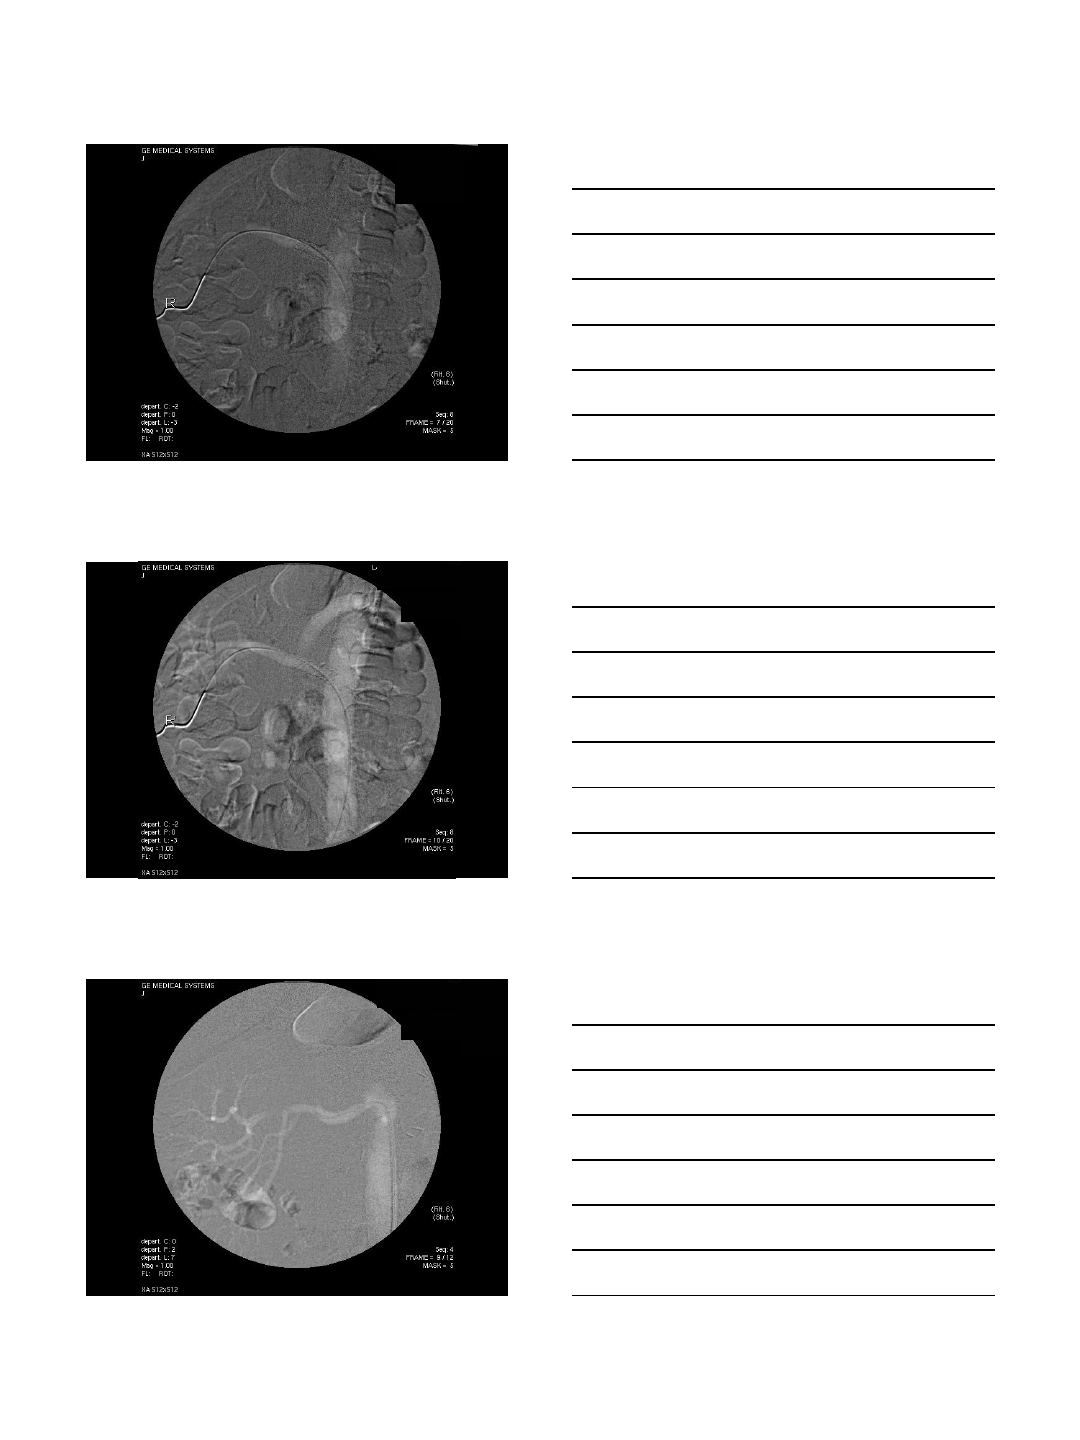

CO2 Portogram in TIPS

TIPS procedures

•AP and oblique views

•Excellent to localize the portal vein

•Wedge injection

•Wedged catheter or balloon catheter

•Gentle injection of 15-20 cc

•Careful in patients with ascites

•Intraparenchymal injection